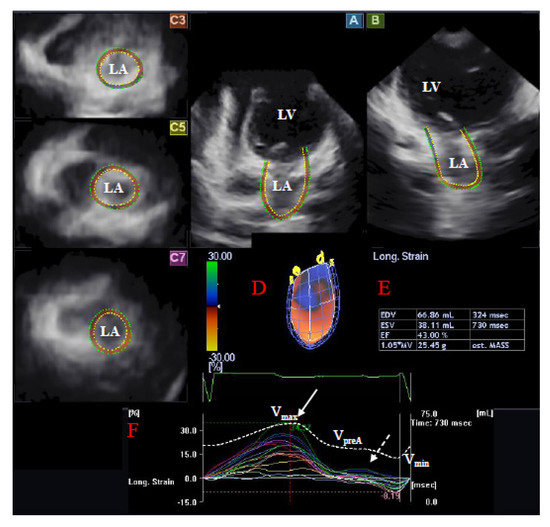

2.3. Three-Dimensional Speckle-Tracking Echocardiography

2.4. Left Atrial 3DSTE-Derived Volumetric Measurements

2.4.1. Reservoir Function

2.4.2. Conduit Function

2.4.3. Active Contraction

2.5. Left Atrial 3DSTE-Derived Strain Measurements